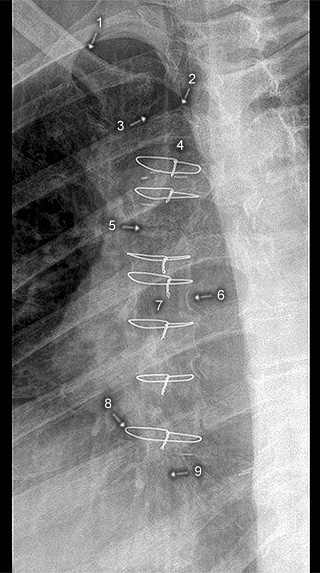

Sternum p.a.

1. Clavicula

2. Jugulum

3. Articulatio sternoclavicularis

4. Manubrium sterni

5. Angulus sterni

6. Incisura costalis

7. Corpus sterni

8. Drahtcerclage

9. Processus xiphoideus